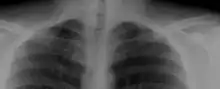

A cervical rib in humans is an extra rib which arises from the seventh cervical vertebra. Their presence is a congenital abnormality located above the normal first rib. A cervical rib is estimated to occur in 0.2%[2] to 0.5%[3] (1 in 200 to 500) of the population.[4] People may have a cervical rib on the right, left or both sides.[5][6]

Most cases of cervical ribs are not clinically relevant and do not have symptoms;[7][8] cervical ribs are generally discovered incidentally, most often during x-rays and CT scans.[3][4][6] However, they vary widely in size and shape,[3] and in rare cases, they may cause problems such as contributing to thoracic outlet syndrome,[7] because of pressure on the nerves that may be caused by the presence of the rib.[7][9]

On imaging, cervical ribs can be distinguished because their transverse processes are directed inferolaterally, whereas those of the adjacent thoracic spine are directed anterolaterally.[11]